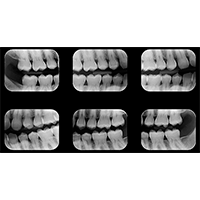

Periapical

Interproximal

Documentação